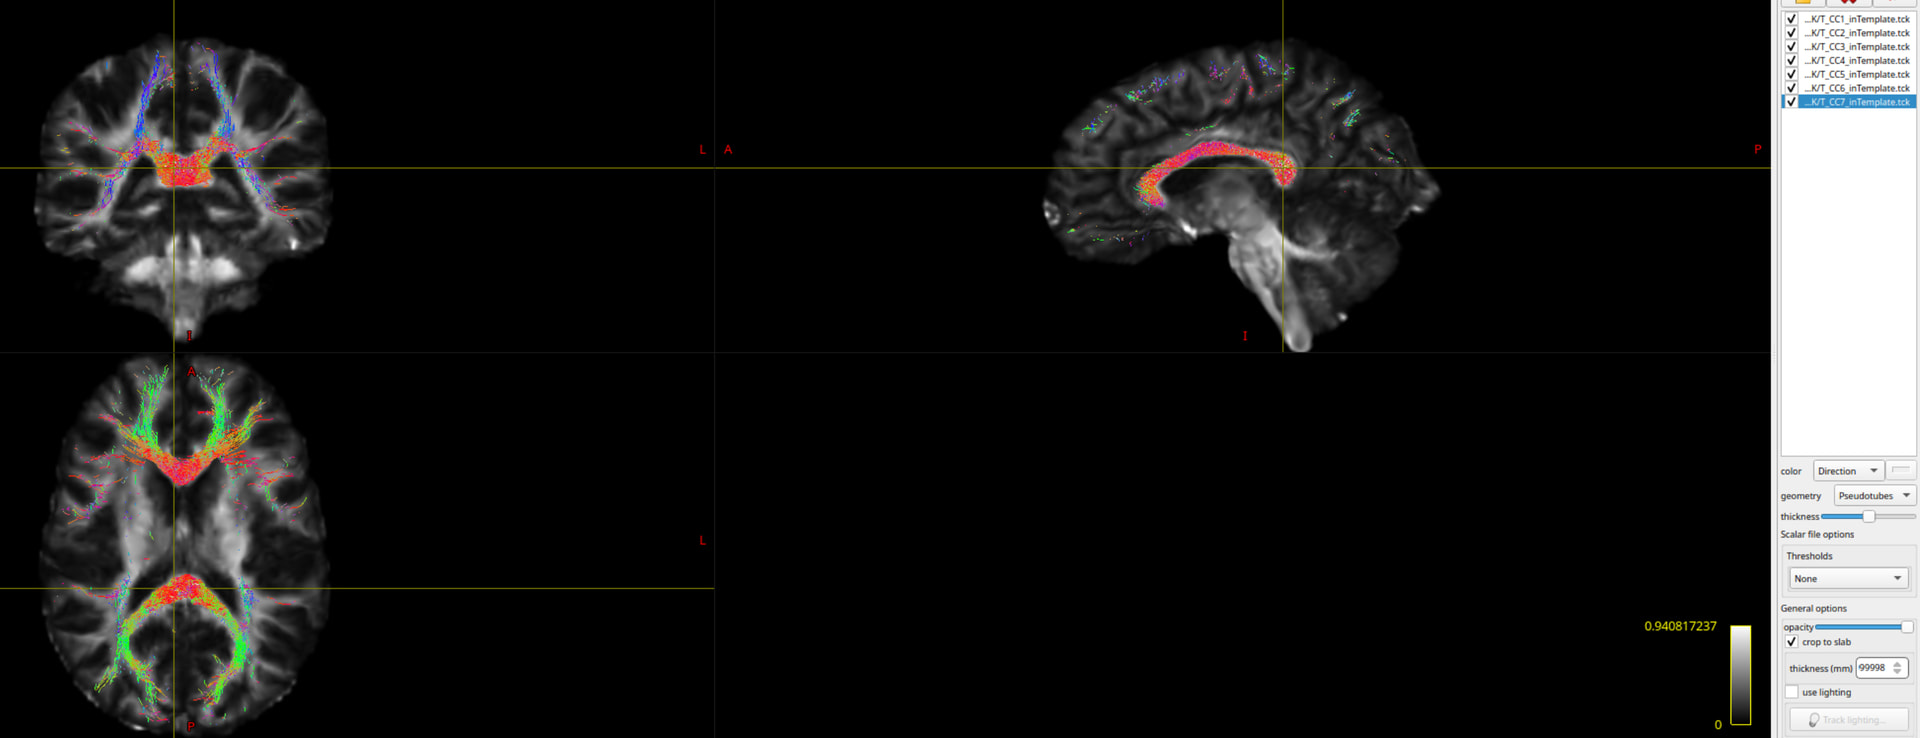

Recently, I am focusing on using big data like ADNI to explore white matter fiber tractography in different groups. I used Mrtrix3 (iFOD2) to generate the whole brain fiber tractography (whole_tract.tck). After that, I used ‘tckconvert‘ command to convert the ‘whole_tract.tck‘ to ‘whole_tract.vtk‘. Then I used the WMA package ( whitematteranalysis | White matter tractography clustering and more… ) to register ‘whole_tract.vtk‘ onto ORG-atlas (registration_atlas.vtk). I have tried to used both “rigid-affine” and “affine + nonrigid“ registration methods, but the results shown in Figure 2 looks like the commissural fibers not following the pattern of corpus callosum. I am not sure what’s wrong with it. My codes are as follows:

I tried to generate the different fiber tracts using WMA, and then register the individual fiber tract onto the template, and using the common mask to extract the voxel-wise DTI metrics. It looks a bit different from TBSS. But now, I need to solve the mismatching problem between the template T1.nii.gz and the registered fiber tracts.